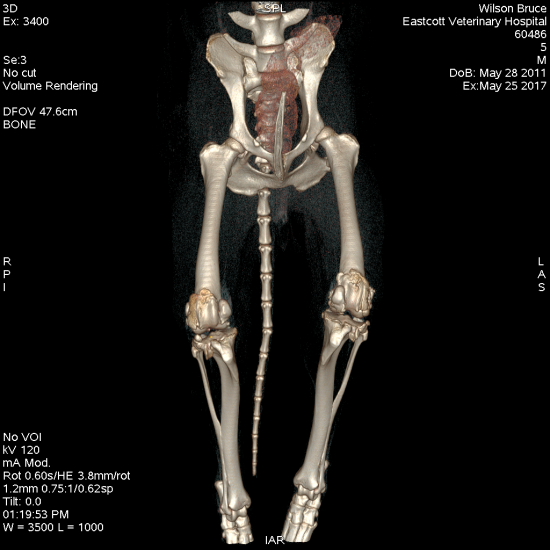

TPLO has been shown to be a robust and reliable procedure for dogs of all sizes. Most dogs are weight bearing well on the operated leg the day following surgery and benefit from the early limb use this allows. The procedure is designed to change the biomechanics of the stifle joint such that it neutralises cranial tibial thrust during the stance phase effectively doing away with the need for a cranial cruciate ligament. TPLO is suitable for dogs at every stage of cruciate disease from early partial tears, acute traumatic cruciate tears to chronic arthritic stifles. We expect 95% of dogs to have a good or excellent outcome following TPLO with a low rate of complications. A recent study by Krotscheck 2016 compared extracapsular suture, tibial tuberosity advancement and TPLO, using force plate assessment at 8 weeks, 6 months and 12 months. Whilst dogs having TTA had slightly better weight bearing at 8 weeks, TPLO was the only surgery able to return dogs to normal weight bearing at 6 and 12 months after surgery at both a walk and a trot. With this evidence we consider TPLO to be the best option for the treatment of cruciate disease in dogs.

Figure 1. Tibial plateau levelling osteotomy using a broad locking plate and screws in a 45kg Labrador